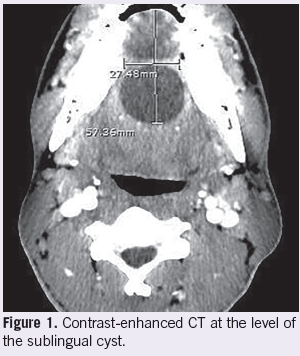

John Chin, MD, MBChB

A 19-year-old African-American male with a history of frenectomy and recurrent sublingual cysts presented to the emergency department for sublingual swelling.